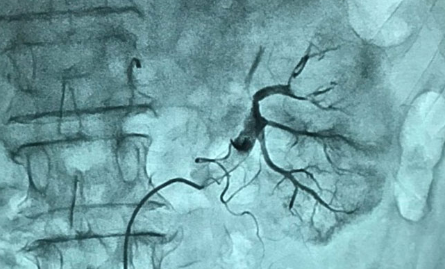

Sáng 1/3, theo thông tin từ Bệnh viện Việt Nam - Thụy Điển Uông Bí (Quảng Ninh), các bác sĩ vừa tiến hành can thiệp lấy huyết khối động mạch thận cho người bệnh bị nhồi máu thận cấp tính trên nền bệnh rung nhĩ.

Bệnh nhân là ông T.V.H (63 tuổi) nhập viện do đau tức mạn sườn trái, đau lan ra sau lưng, tê hai chân. Kết quả khám lâm sàng, chụp cắt lớp vi tính (CT scanner) ổ bụng cho thấy ông H. bị tắc mạch thận trái, cần can thiệp, lấy huyết khối động mạch thận.

Các bác sĩ đánh giá việc lấy huyết khối nhanh chóng có vai trò rất lớn trong việc bảo toàn chức năng cho thận. "Nếu để quá lâu, máu không được lưu thông, bệnh nhân có thể suy thận khiến bộ phận này mất hoàn toàn chức năng", ThS.BS Hoàng Minh Quang, Bệnh viện Việt Nam - Thụy Điển Uông Bí, cho biết.

Nhồi máu thận cấp tính là tình trạng xuất hiện cục máu đông ở 1 hoặc cả 2 động mạch cung cấp máu cho thận. Điều này làm giảm tưới máu thận và có thể dẫn đến tắc mạch thận cấp tính, gây mất chức năng thận.

Trước đây, người bệnh tắc mạch thận thường được điều trị nội khoa, mất nhiều thời gian nhưng hiệu quả không cao. Hiện nay, bác sĩ ứng dụng kỹ thuật cao dưới sự hỗ trợ của hệ thống máy chụp hình số hóa xóa nền DSA, giúp việc lấy huyết khối động mạch diễn ra nhanh chóng, huyết khối được lấy ra nhằm tái thiết lập lại hệ tuần hoàn cho thận.